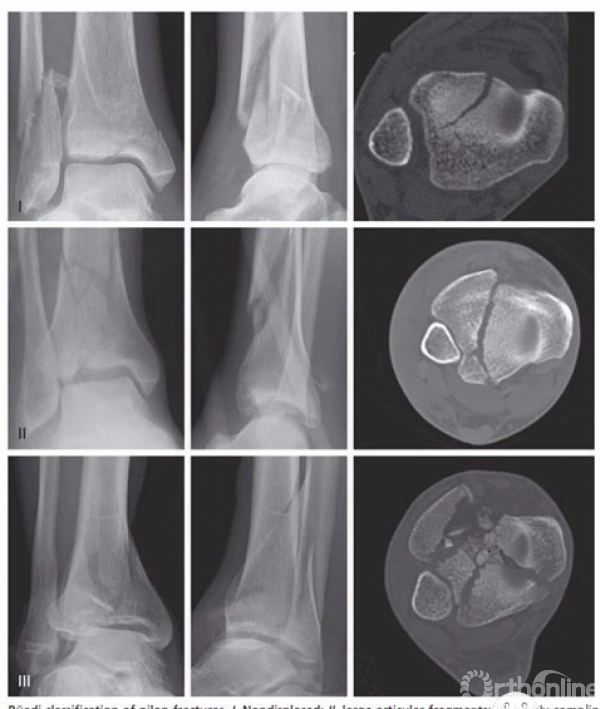

Haraguchi等根据胫骨远端关节面水平的CT图像显示的后踝骨折线方向,将后踝骨折分为三型:

(二)Bartonicek分型

Bartonicek等在CT扫描和三维重建的基础上,根据骨块位置、形状、大小和胫骨腓切迹完整性等因素,将后踝骨折分为四型:

1型,切迹外骨折,胫骨腓切迹未受累;

2型,后外侧骨折,骨折主要累及胫骨腓切迹的后1/4~1/3;

3型,后踝两部分骨折,后内侧骨折线延伸至内踝后丘或丘间沟,外侧骨折块主要累及胫骨腓切迹的后1/4~1/3;

4型,后外侧大三角形骨块,骨折线主要累及胫骨远端内后缘和腓切迹的后1/3~1/2,呈三角形。

以上四型的发病率依次为8%、52%、28%、13%。骨折累及胫骨远端关节面的平均比例依次为9%、14%、24%、29%。

这一分型体现了后踝骨折的受伤机制,即从扭转暴力向轴向暴力转变,暴力强度逐渐增加,损伤程度逐渐加重的趋势和特点。